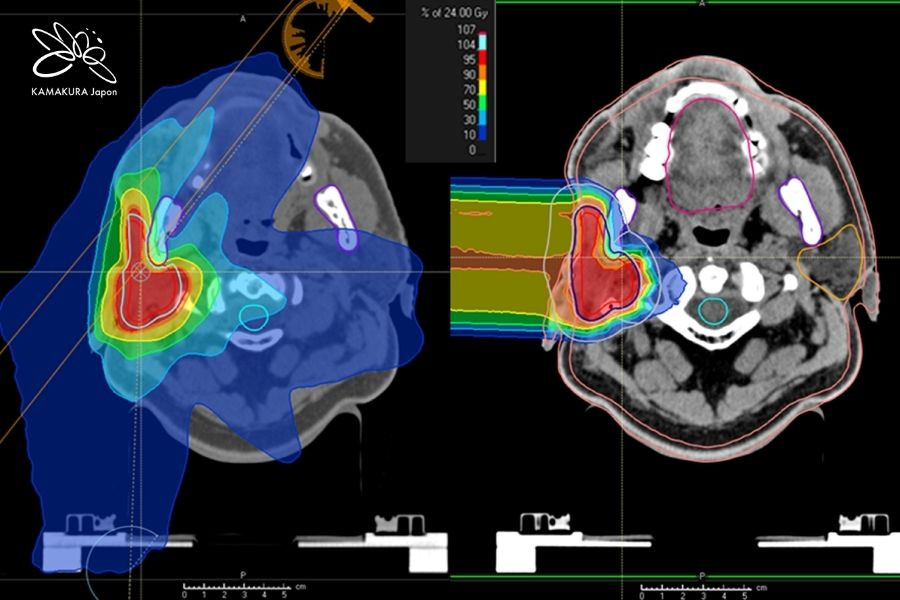

- Kỹ thuật quét tia 3D (3D beam scanning) kết hợp định vị theo hơi thở (respiratory-gated irradiation) giúp chiếu tia chính xác đến từng mô ung thư

- Rotating gantry superconducting (từ 2018): chiếu tia ion carbon từ mọi hướng, nâng cao hiệu quả điều trị và giảm tác dụng phụ

- Quét tia 3D và định vị hô hấp: chiếu tia chính xác, bảo vệ mô lành

- Rotating gantry superconducting: chiếu tia từ mọi hướng, tối ưu hóa điều trị